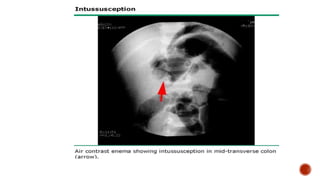

 Bowel enema - barium has been gold standard (crescent sign, filling defect) but air

Barium enema showed filling

defect with crab's claw sign at

the mid transverse colon